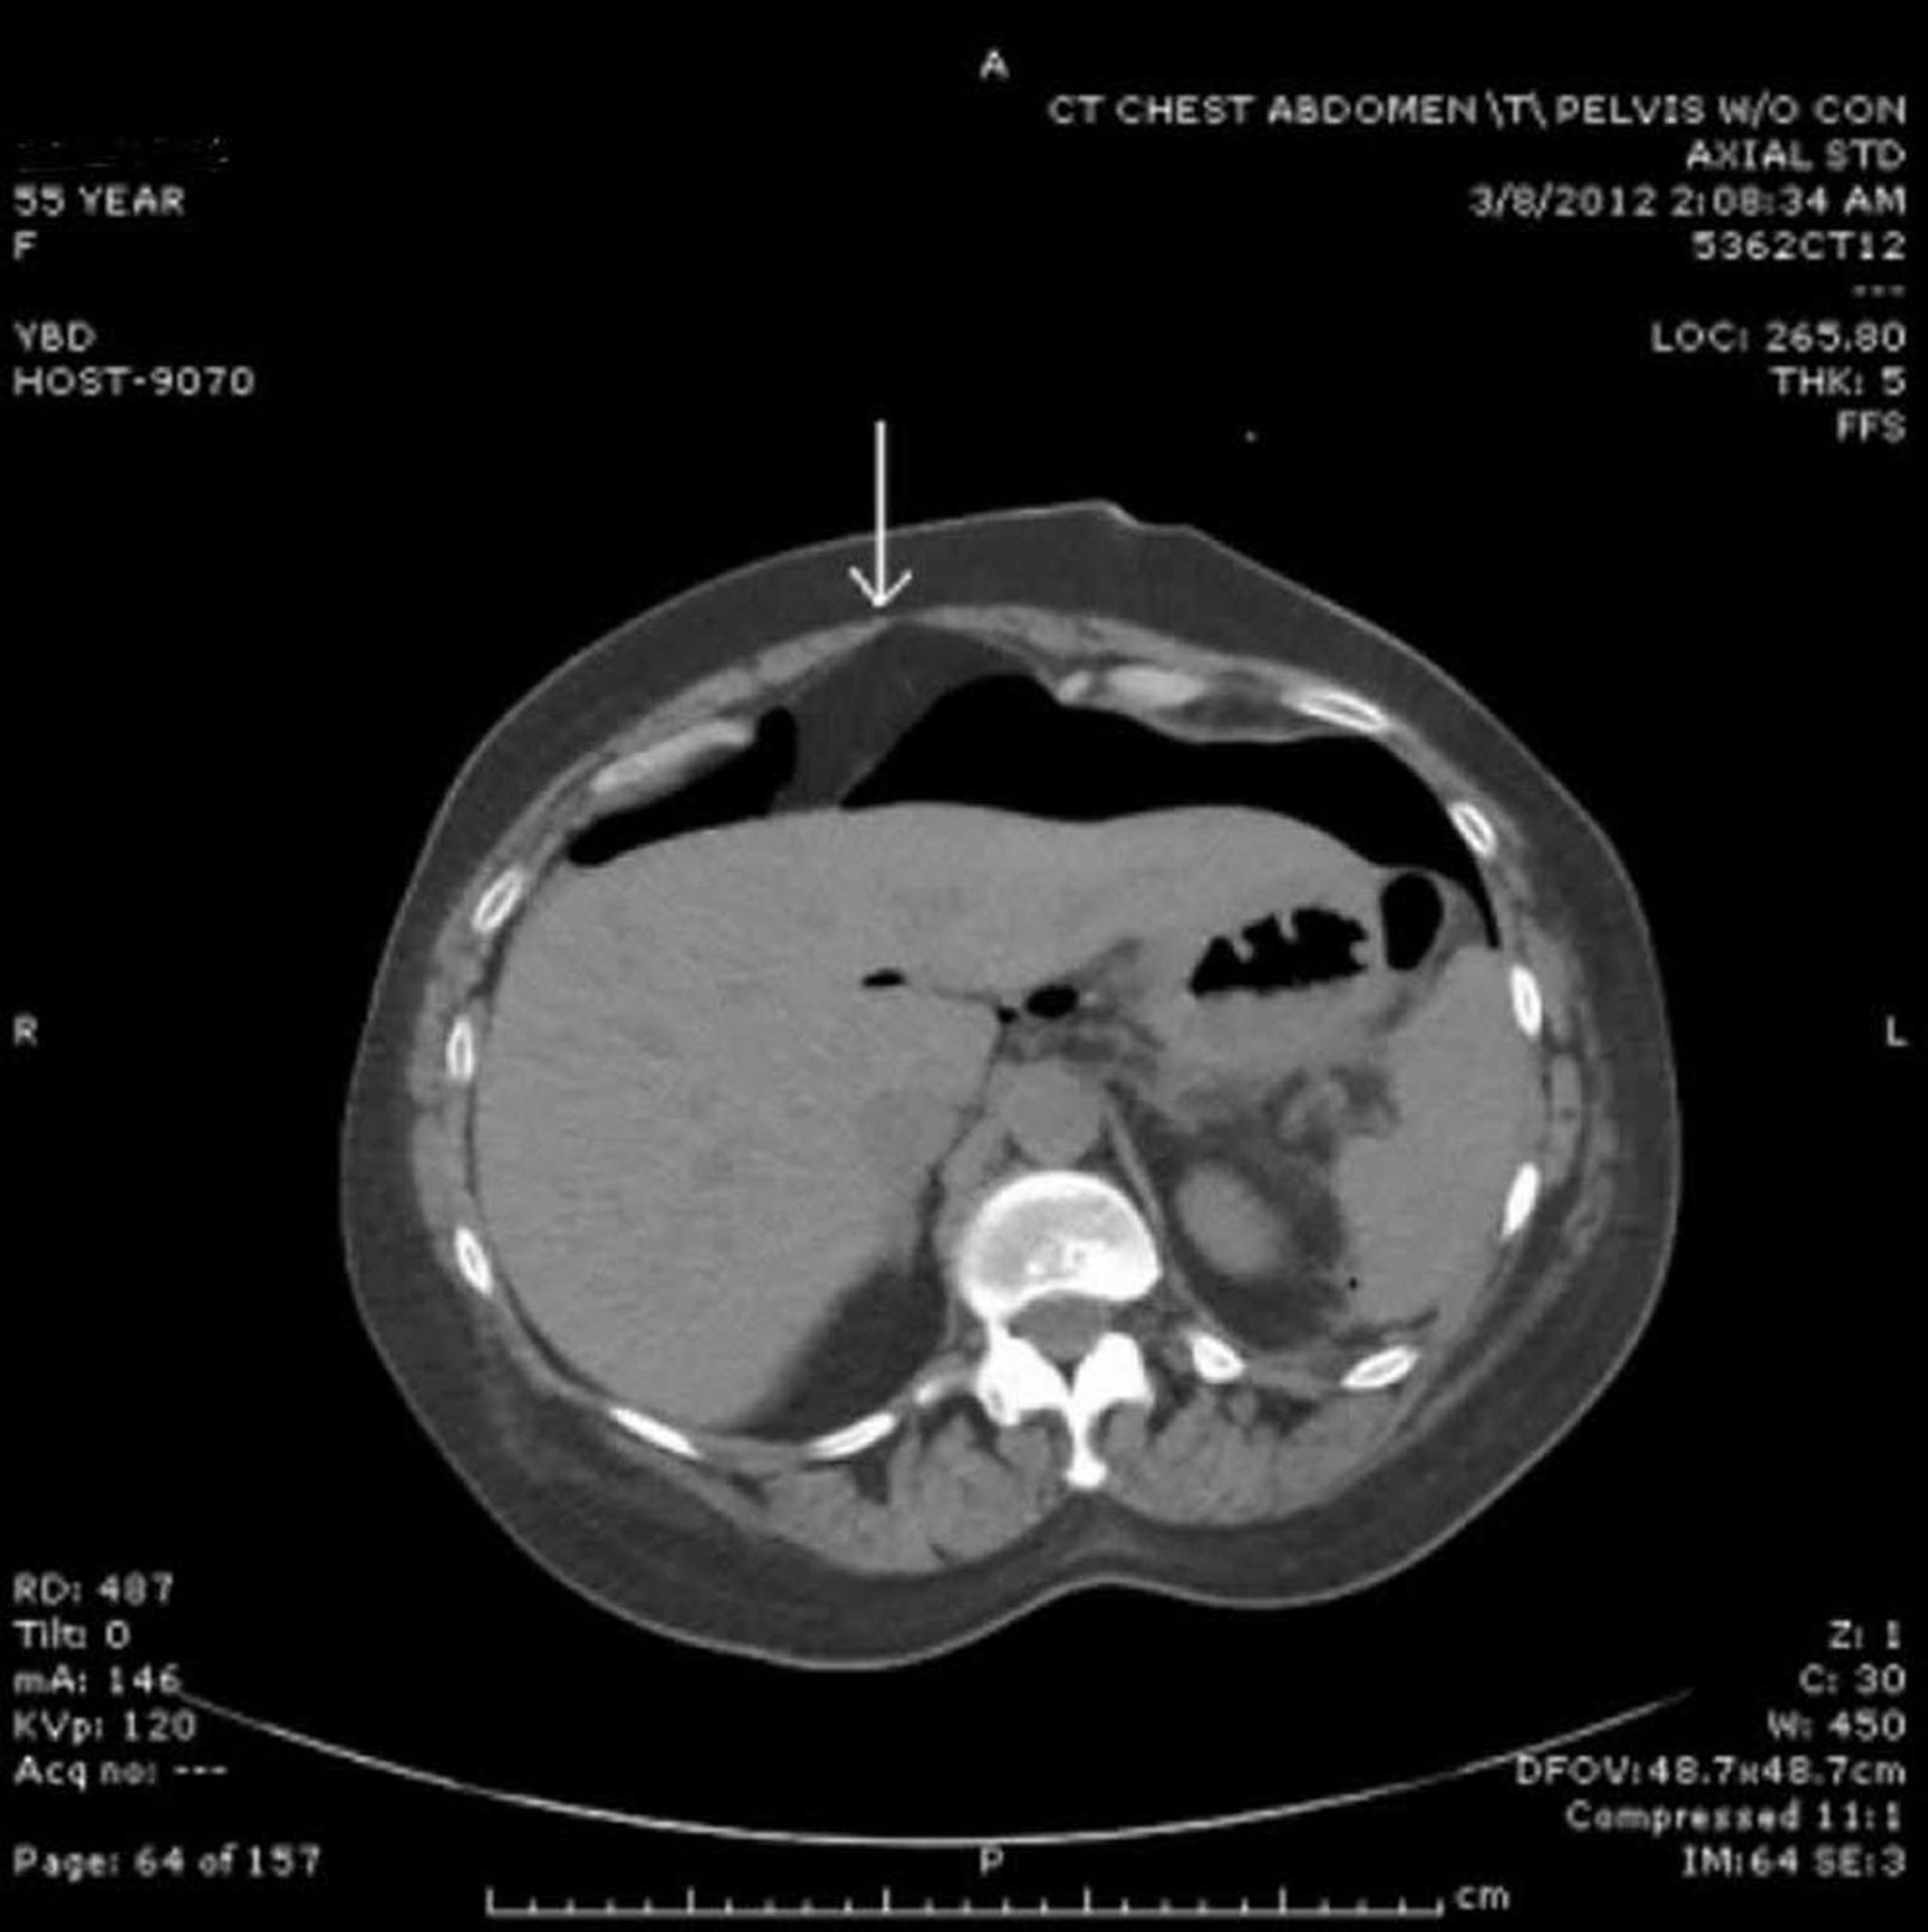

TC con aria libera nel peritoneo

L'aria libera è vista anteriormente al fegato. La freccia indica il legamento falciforme.

Image provided by Parswa Ansari, MD.